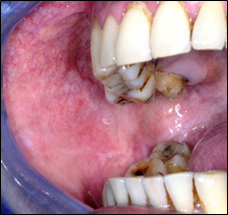

Leukoplakia

a predominantly white, non-scrapable lesion of the oral mucosa that cannot be characterized clinically or histologically as any other definable lesión.15 This lesion is seen most often in middle aged and older men. Depending on the clinical presentation, leukoplakia can be divided in to homogenous and non-homogenous forms.16 Homogenous form displays a uniform pattern of reaction throughout lesion with a uniform white patch and shallow ridges in the epithelium17 (Figure 1). The non-homogenous form is of 3 types (1) Speckled with mixed white and red appearance on the surface but predominantly white (2) Nodular with small polypoid outgrowth (3) Verrucous with wrinkled or corrugated surface appearance. Common site of occurrence is commissure, buccal mucosa, lips, tongue, palate, alveolar ridge, floor of mouth, gingiva.6